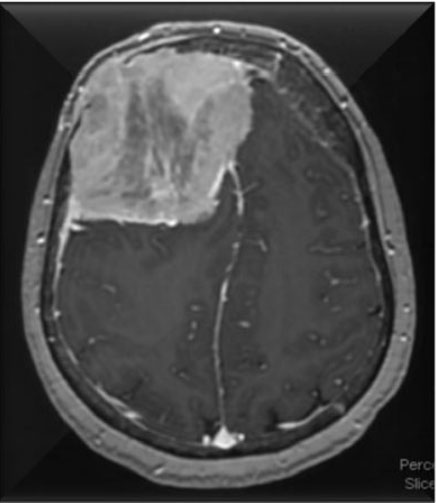

Figure 2: Axial T1 view showing heterogeneous enhancement and leftward displacement of the falx. There is some destruction of the overlying right frontal calvarium.

On examination, her vitals were stable and her laboratory work-up revealed mild normocytic anemia with hemoglobin of 11.2 g/dL but normal creatinine and calcium levels. A physical examination revealed a right frontoparietal swelling approximately 8 × 6 cm in size. Computed tomography of the head was most concerning, showing a large expansile heterogenous right frontal mass eroding the skull and protruding outward (Figure 1, Figure 2, Figure 3). There was frontal vasogenic edema, mass effect, generalized cerebral sulcal effacement, as well as effacement of the frontal horns of the lateral ventricles and suprasellar cistern. Additionally, scattered sub-centimeter calvaria lytic foci were noted.